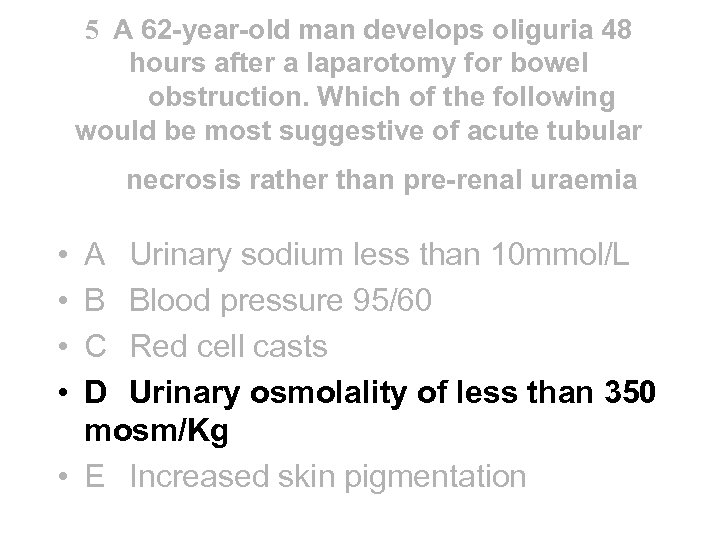

5 A 62 -year-old man develops oliguria 48 hours after a laparotomy for bowel obstruction. Which of the following would be most suggestive of acute tubular necrosis rather than pre-renal uraemia • • A Urinary sodium less than 10 mmol/L B Blood pressure 95/60 C Red cell casts D Urinary osmolality of less than 350 mosm/Kg • E Increased skin pigmentation

5 A 62 -year-old man develops oliguria 48 hours after a laparotomy for bowel obstruction. Which of the following would be most suggestive of acute tubular necrosis rather than pre-renal uraemia • • A Urinary sodium less than 10 mmol/L B Blood pressure 95/60 C Red cell casts D Urinary osmolality of less than 350 mosm/Kg • E Increased skin pigmentation

5 A 62 -year-old man develops oliguria 48 hours after a laparotomy for bowel obstruction. Which of the following would be most suggestive of acute tubular necrosis rather than pre-renal uraemia • • A Urinary sodium less than 10 mmol/L B Blood pressure 95/60 C Red cell casts D Urinary osmolality of less than 350 mosm/Kg • E Increased skin pigmentation

5 A 62 -year-old man develops oliguria 48 hours after a laparotomy for bowel obstruction. Which of the following would be most suggestive of acute tubular necrosis rather than pre-renal uraemia • • A Urinary sodium less than 10 mmol/L B Blood pressure 95/60 C Red cell casts D Urinary osmolality of less than 350 mosm/Kg • E Increased skin pigmentation

Incipient v established ATN • Incipient (tubules still function) U/P osmolality • >1. 5 Urine Na • <20 mmol/l Urine Osm • 350 -1000 m. Osm/kg • Established (tubules don’t function) • <1. 1 • >40 mmol/l • <350 m. Osm/kg NB - red cell casts are a feature of active GN not ATN - BP 95/60 mm. Hg reflects volume depletion or shock not necessarily ATN - skin pigmentation is a feature of CRF not ATN Nephrologists don’t use these criteria at all!

Incipient v established ATN • Incipient (tubules still function) U/P osmolality • >1. 5 Urine Na • <20 mmol/l Urine Osm • 350 -1000 m. Osm/kg • Established (tubules don’t function) • <1. 1 • >40 mmol/l • <350 m. Osm/kg NB - red cell casts are a feature of active GN not ATN - BP 95/60 mm. Hg reflects volume depletion or shock not necessarily ATN - skin pigmentation is a feature of CRF not ATN Nephrologists don’t use these criteria at all!